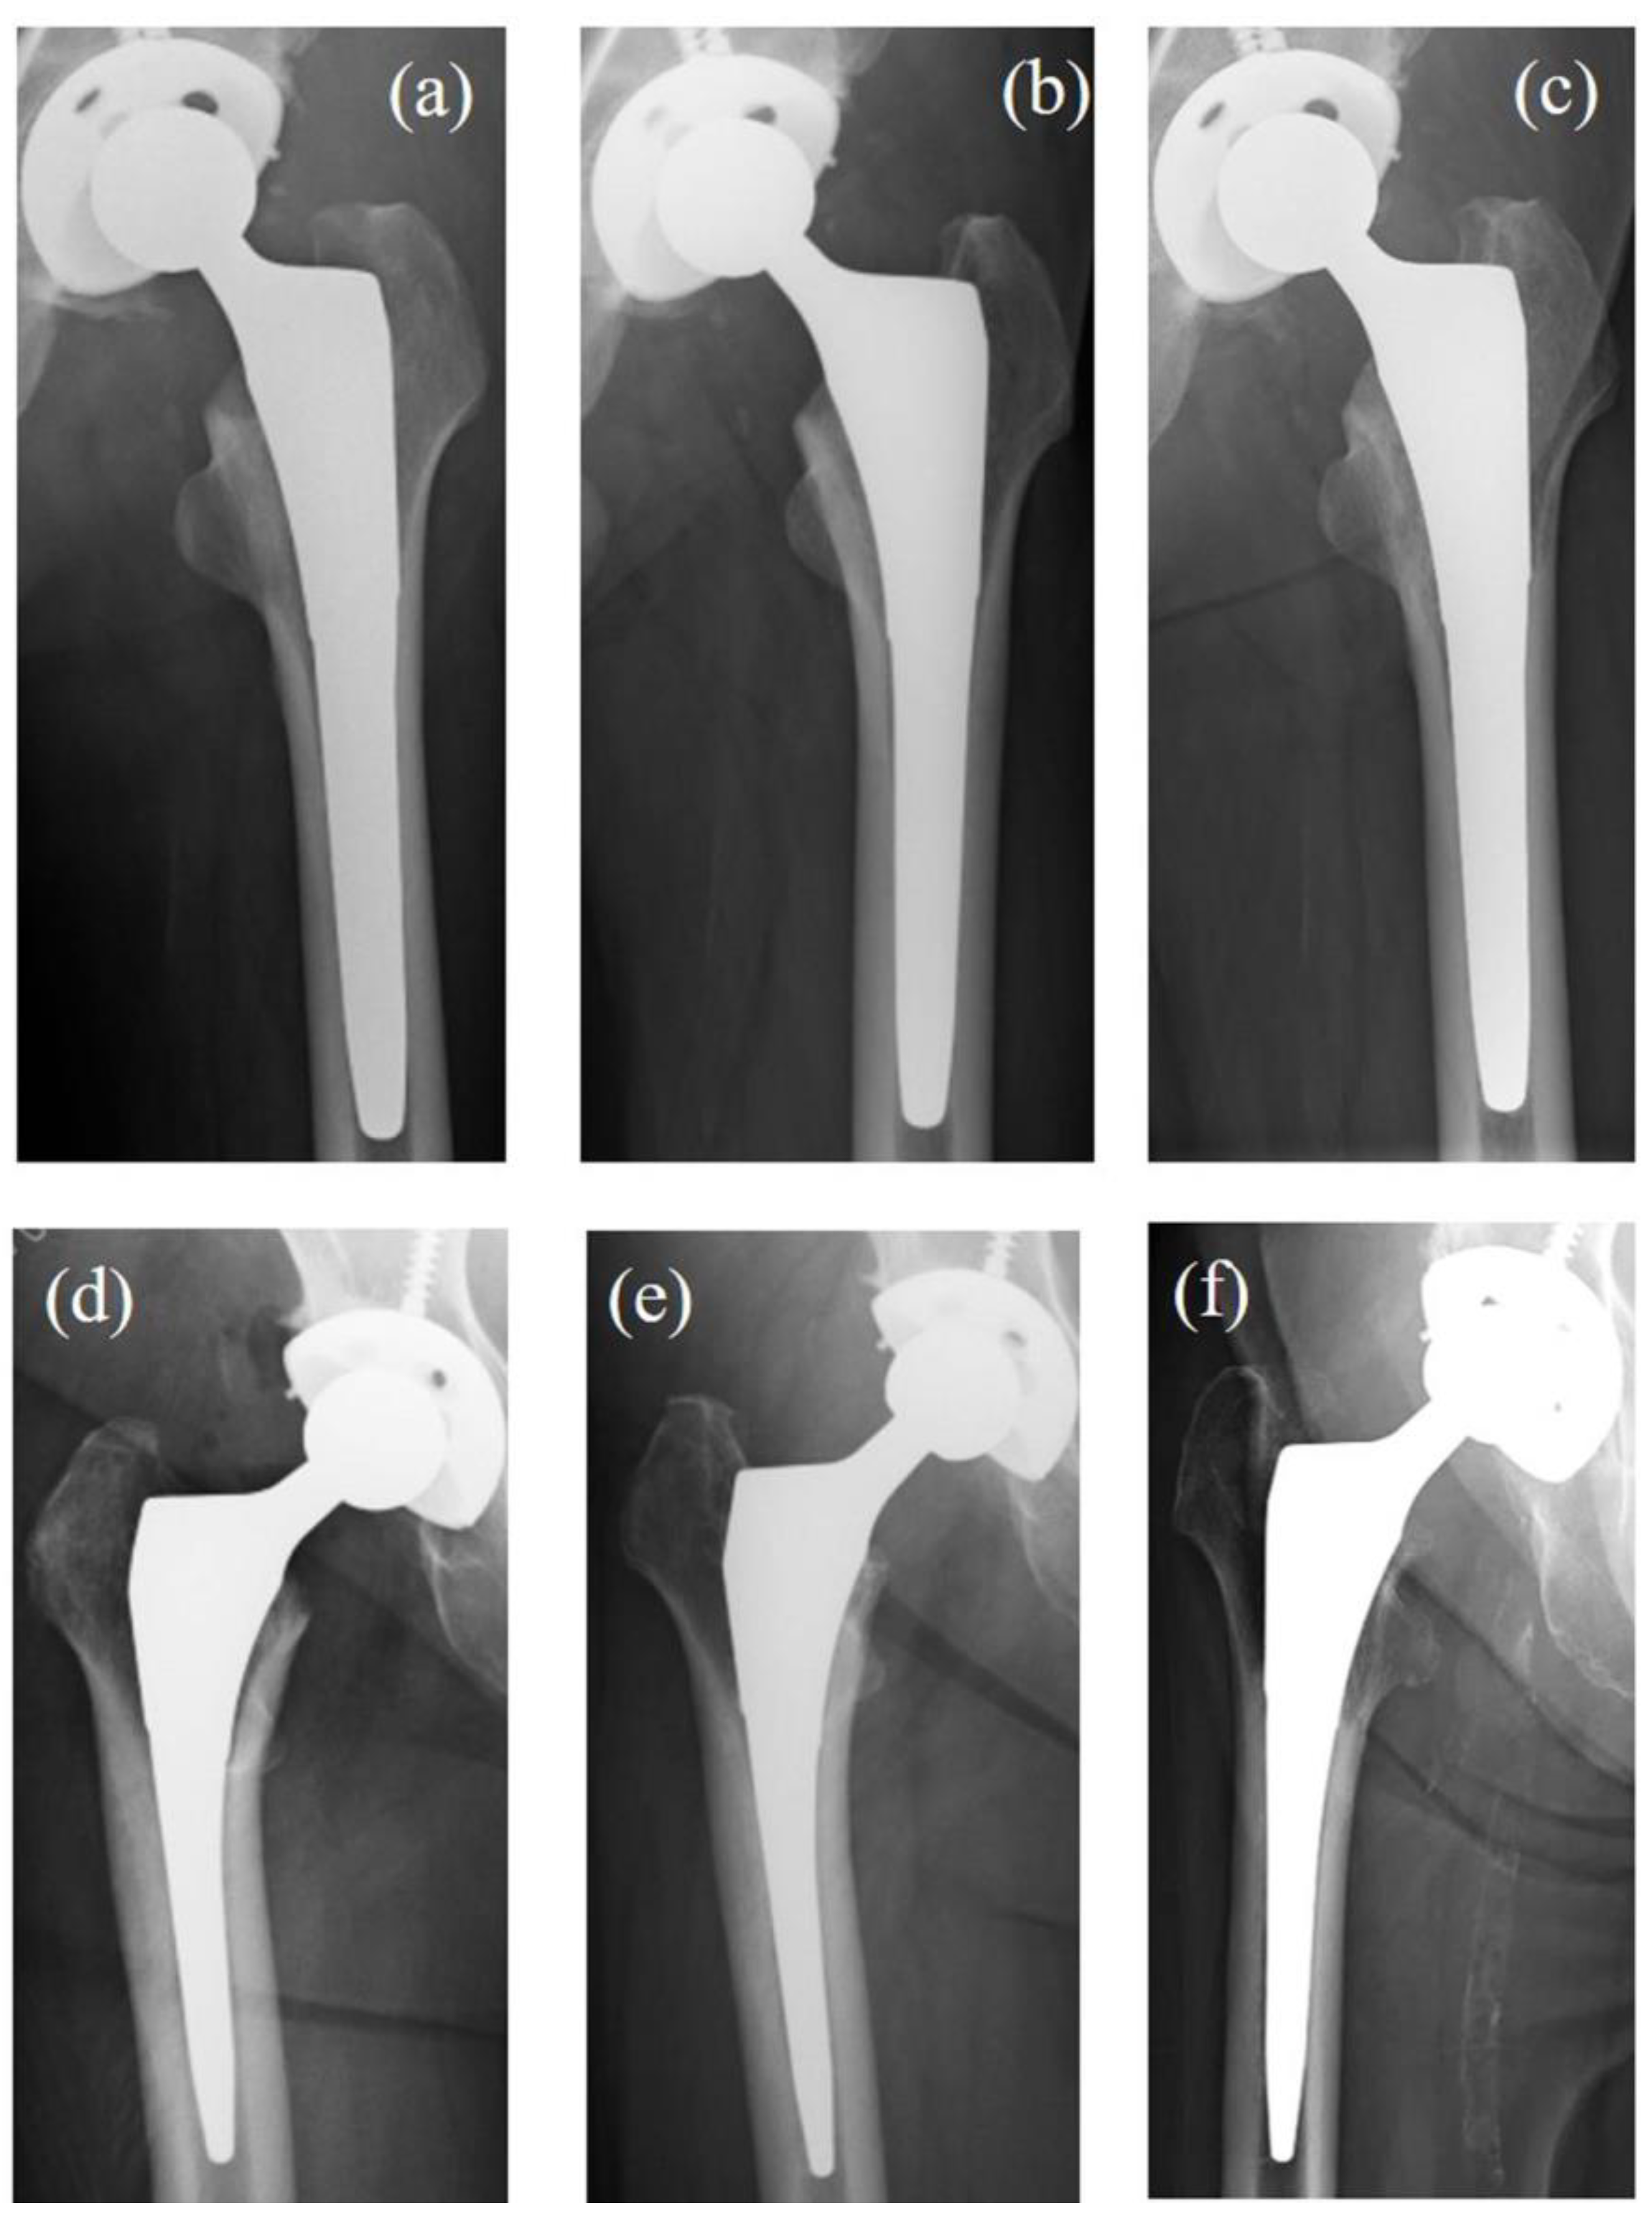

Figure 4 presents two cases of THA performed using TNS stems: one without SS and one with progressive SS.

Figure 4.

The X-rays of two cases of THA were performed using a TNS stem. Case 1 (a–c): A 58-year-old male diagnosed with idiopathic osteonecrosis of the left femoral head. No SS was observed at the final follow-up. (a) X-ray 3 weeks post operation. (b) X-ray 52 weeks post operation. (c) X-ray 94 months post operation. Case 2 (d–f): A 68-year-old female diagnosed with right hip osteoarthritis. Progressive SS was observed over time. (d) X-ray 3 weeks post operation. (e) X-ray 52 weeks post operation, showing rounding of the proximal femoral neck, consistent with first SS. (f) X-ray 85 months post operation, showing medial cortical bone resorption extending below the lesser trochanter, consistent with third SS. THA: total hip arthroplasty. SS: stress shielding.

Case 1: A 58-year-old male diagnosed with idiopathic osteonecrosis of the left femoral head. No evidence of SS was observed at the final follow-up (Figure 4a–c).

Case 2: A 68-year-old female diagnosed with right hip osteoarthritis. At 52 months post operation, radiographic findings showed rounding of the proximal femoral neck, classified as first-degree SS. By the final follow-up, medial cortical bone resorption below the level of the lesser trochanter was noted, classified as third-degree SS (Figure 4d–f).